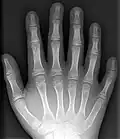

Полидактили́я (др.-греч. πολύς — много + δάκτυλος — палец, синоним — многопалость), также известная как гипердактилия — порок развития, характеризующейся бо́льшим, чем в норме, количеством пальцев на руках или ногах у человека, собак, котов и лошадей. Противоположным отклонением является олигодактилия.

У людей и животных она может проявляться как на одной, так и на обеих руках. Обычно дополнительный палец представляет собой небольшой кусочек мягкой ткани, которую можно удалить. Иногда это просто кость без суставов; очень редко лишний палец бывает полноценным. Дополнительный палец чаще всего образуется со стороны мизинца, реже - на стороне большого пальца и очень редко - между средними пальцами. Обычно лишний палец является аномальным разветвлением обычного пальца, редко возникает на запястье, как обычный палец.